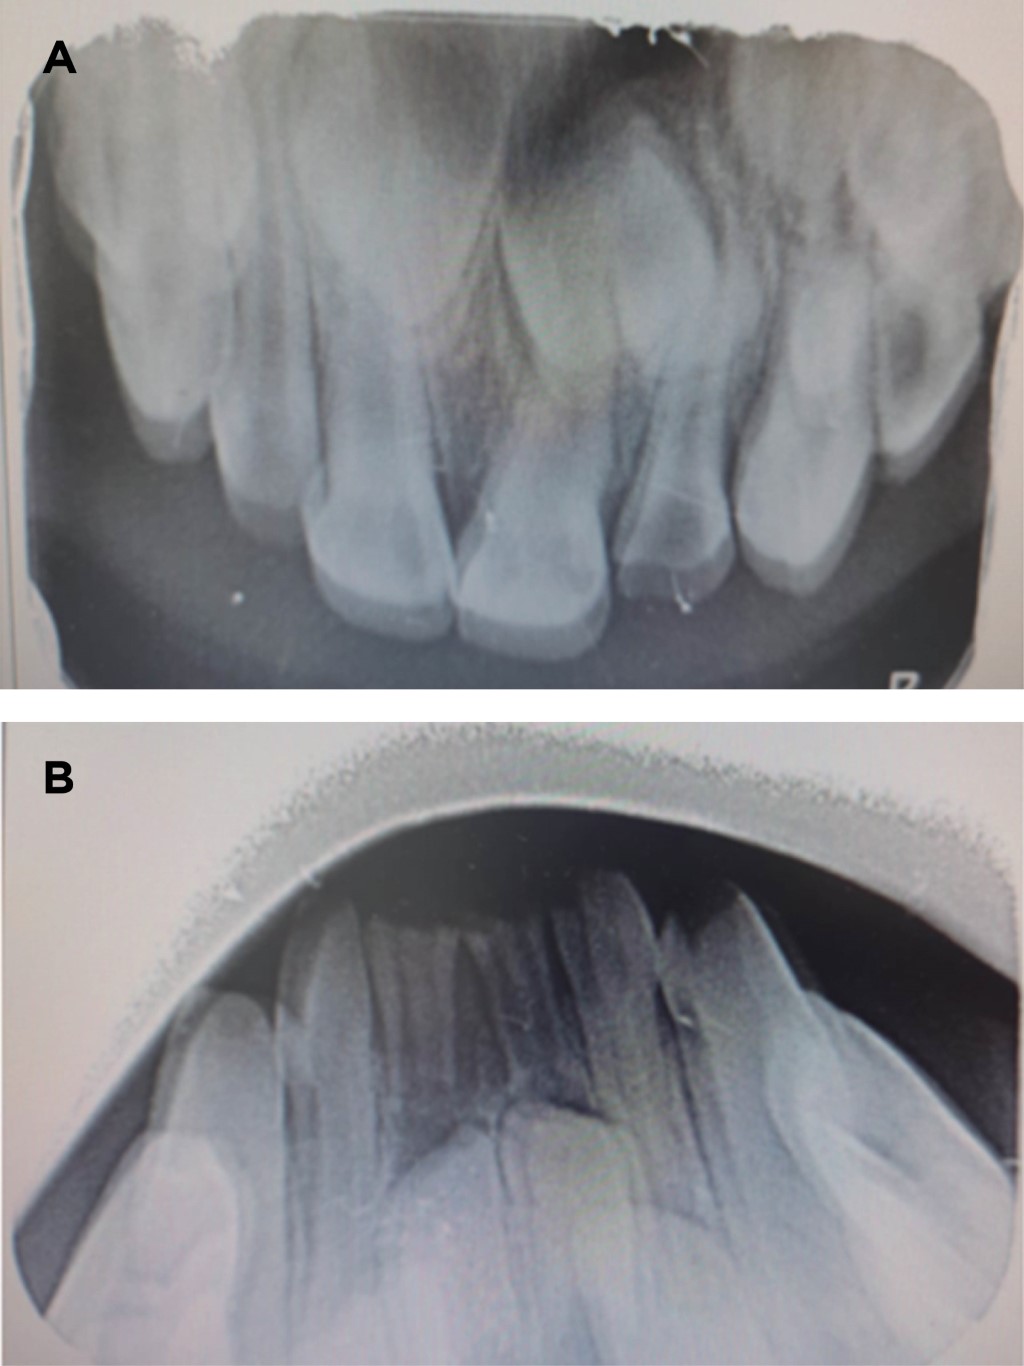

Se toman radiografías oclusales superior e inferior (Figura 1), por las imágenes y la clínica se determina un diagnóstico de caries temprana de la infancia con la necesidad de realizar la extracción del OD 62 durante la cita debido a la imposibilidad de restaurar y el mal pronóstico que presenta.